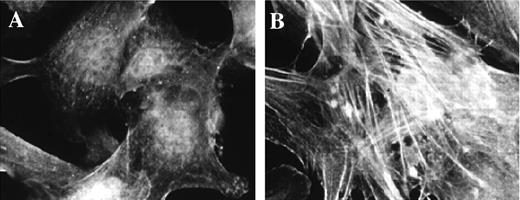

Figure 2.

Addition of TGF-β1 induced pericyte expression of α-SMA. Shown are bovine retinal pericytes cultured as described and stained for α-SMA, after being grown in DMEM with 10% serum (A) or in low serum in the presence of 1 ng/mL TGF-β (B), which caused an increase in the formation of α-SMA-containing stress fibers.